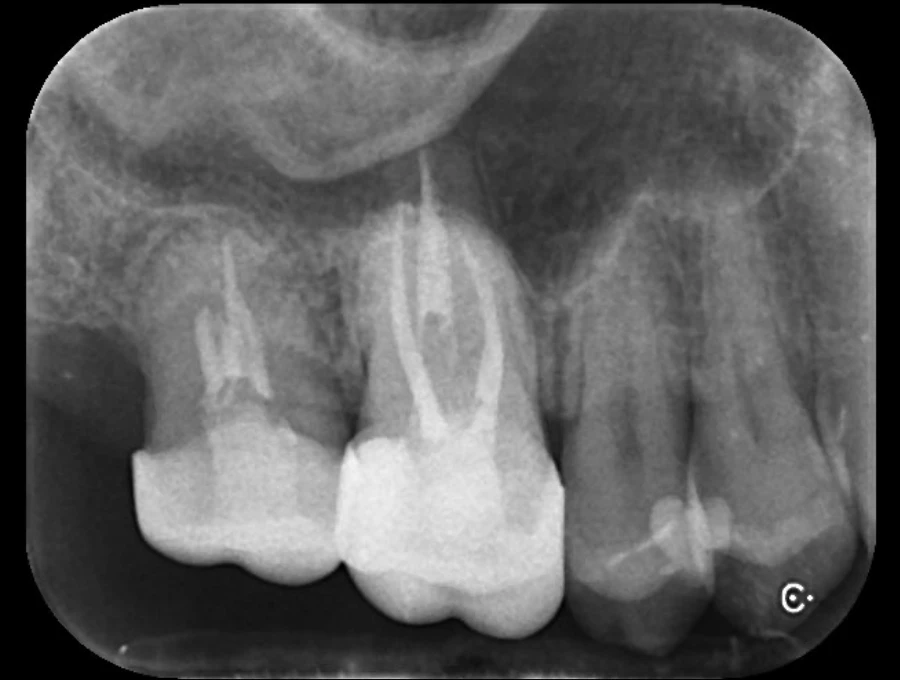

Case.02

治療前

治療後

| 主訴 | むし歯で歯が欠けてしまった。 |

| 治療期間 | 約6ヶ月 |

| 治療費 | 約¥100,000(被せ物代別) |

| 治療内容 | むし歯により抜歯となった部位(右上奥歯)に親知らずを移植。 |

| 治療のリスク | 移植歯がうまく定着しない可能性があります。また、長期的には△。 |